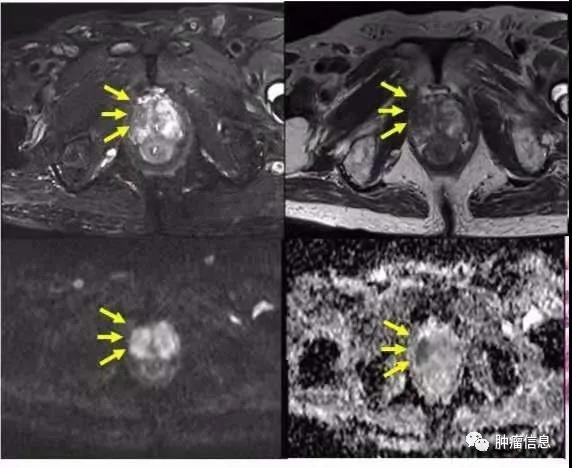

右外下前列腺癌